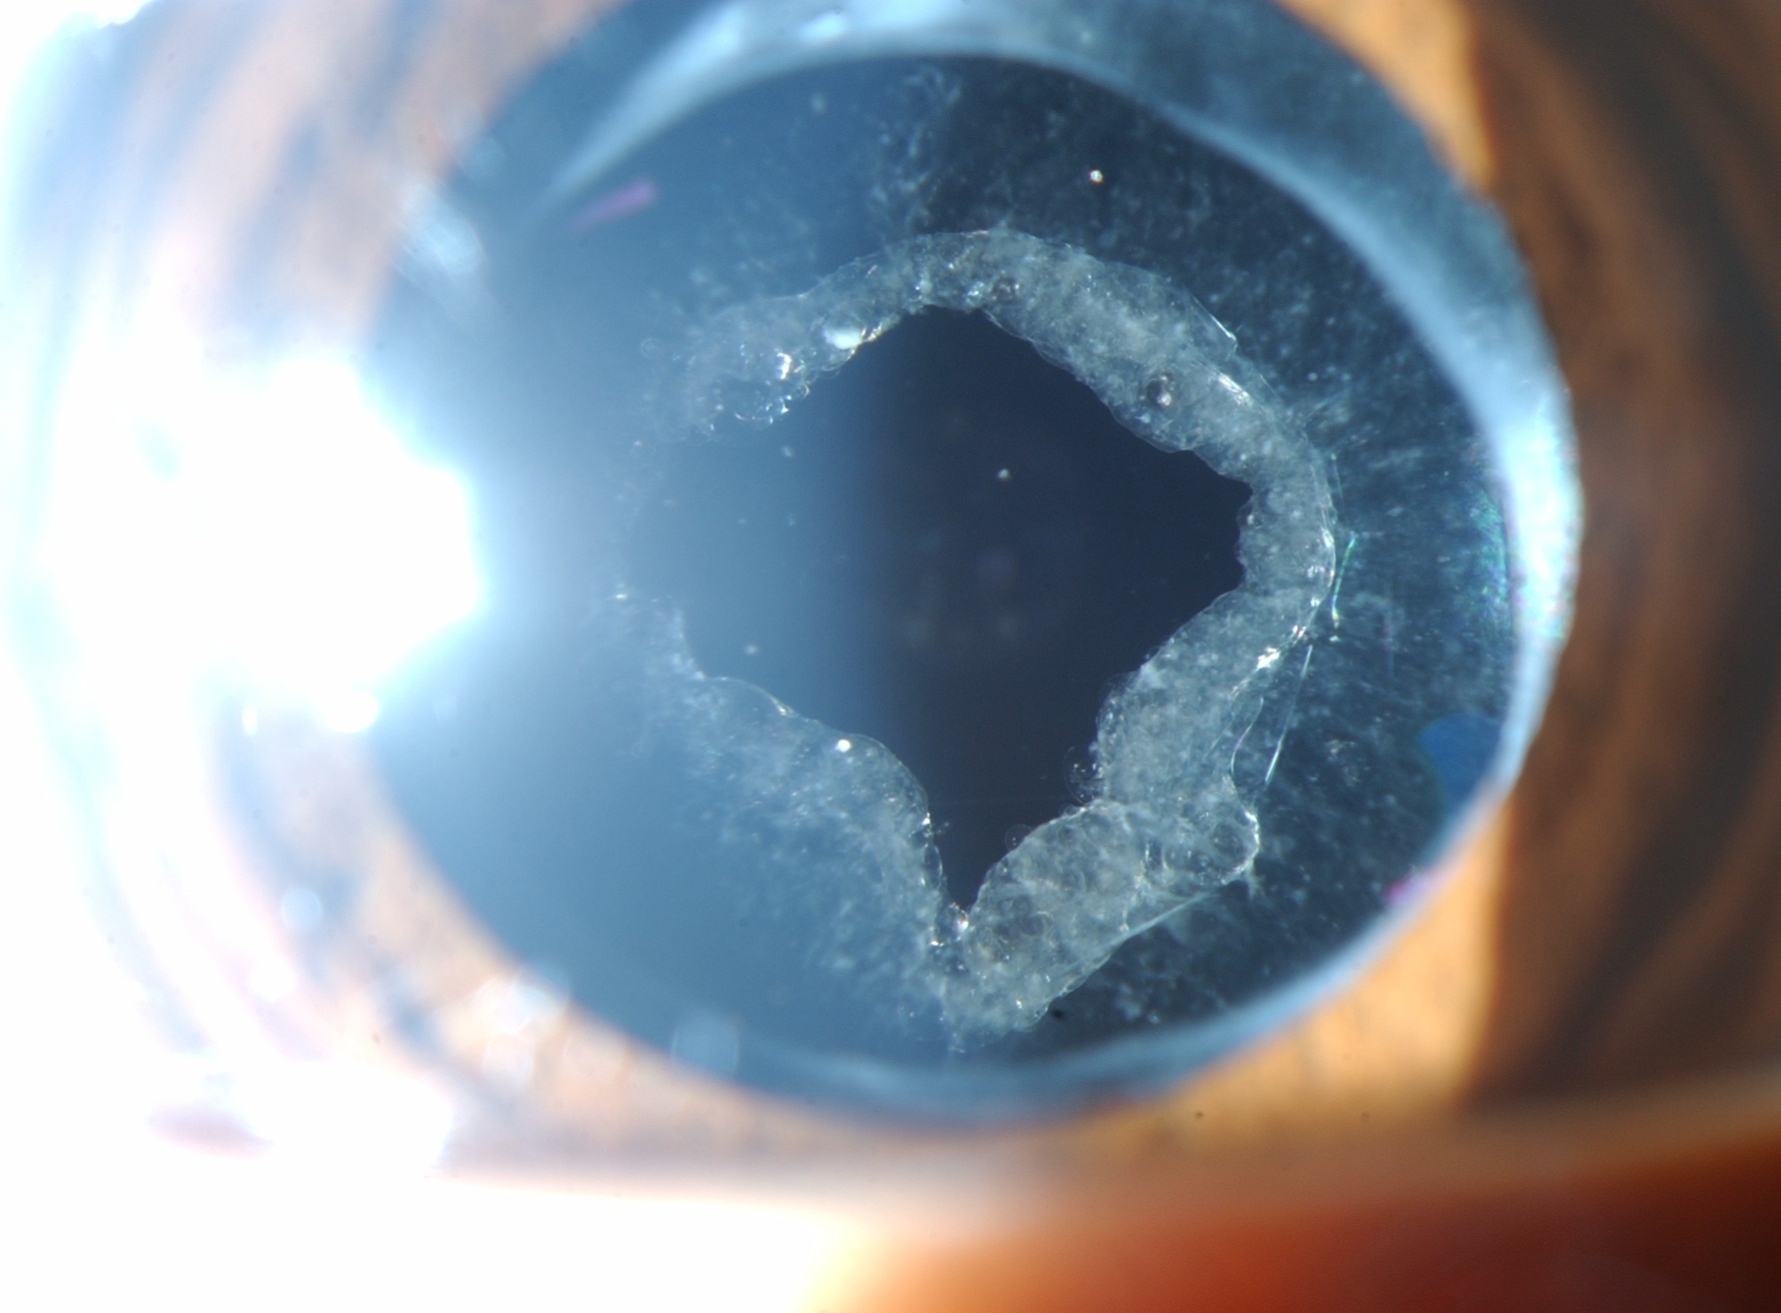

YAG Laser Treatment

YAG laser treatment is a non-invasive procedure used to treat various eye conditions, including post-cataract complications and certain types of glaucoma. This advanced laser technique is highly effective in restoring clear vision and improving eye health. The procedure involves using a specialized laser to remove clouded lens capsules that may develop after cataract surgery, ensuring optimal visual clarity. YAG laser therapy is also utilized in selective laser trabeculoplasty (SLT) to reduce intraocular pressure in glaucoma patients. The treatment is quick, pain-free, and performed on an outpatient basis, requiring minimal recovery time. Our expert ophthalmologists ensure precise laser application for maximum effectiveness and safety. Patients undergoing YAG laser therapy experience immediate improvements in vision quality. Post-procedure care includes follow-up evaluations to monitor results and ensure long-term benefits. With cutting-edge technology and skilled professionals, we provide top-tier YAG laser treatments for enhanced eye health and vision clarity.